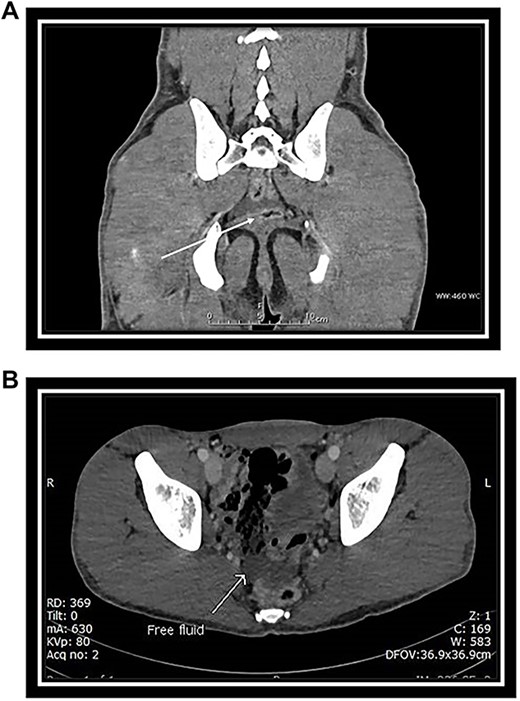

CT scan of abdomen and pelvis with IV contrast was performed (Fig. 4A and B).

(A) Venous phase axial CT scan showing minimal amount of free fluid in the Douglas pouch (retro-vesical). (B) Venous phase coronal CT scan showing minimal amount of free fluid in the Douglas pouch (retro-vesical).

Mild free fluid in the pelvis.

No intra-abdominal solid organ injury.

No free air.

No bony injuries.